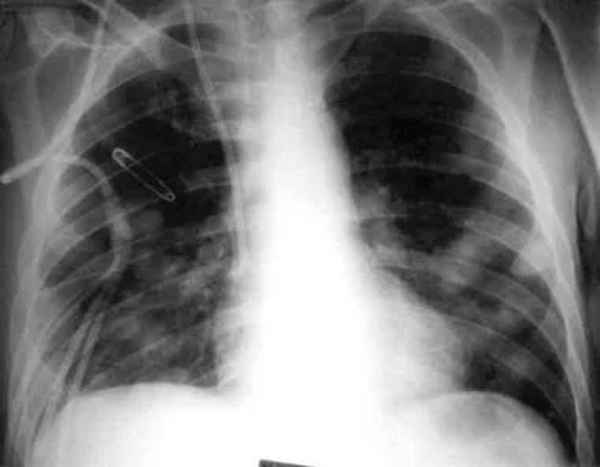

可能会观察到斑片状浸润,结节(见图1),实变,空洞或胸腔积液。

纵隔淋巴结肿大在地方性真菌肺炎患者中很常见。淋巴结肿大可以是单侧或双侧。感染曲霉菌引起中性粒细胞减少的患者(60%),常见磨玻璃影包围肺结节,称为“晕征” 。

图1 胸部X线片示多发肺结节。因慢性粒细胞白血病进行移植后,该患者接受皮质类固醇激素治疗。对支气管肺泡灌洗液真菌培养后显示曲霉菌和其他菌种。